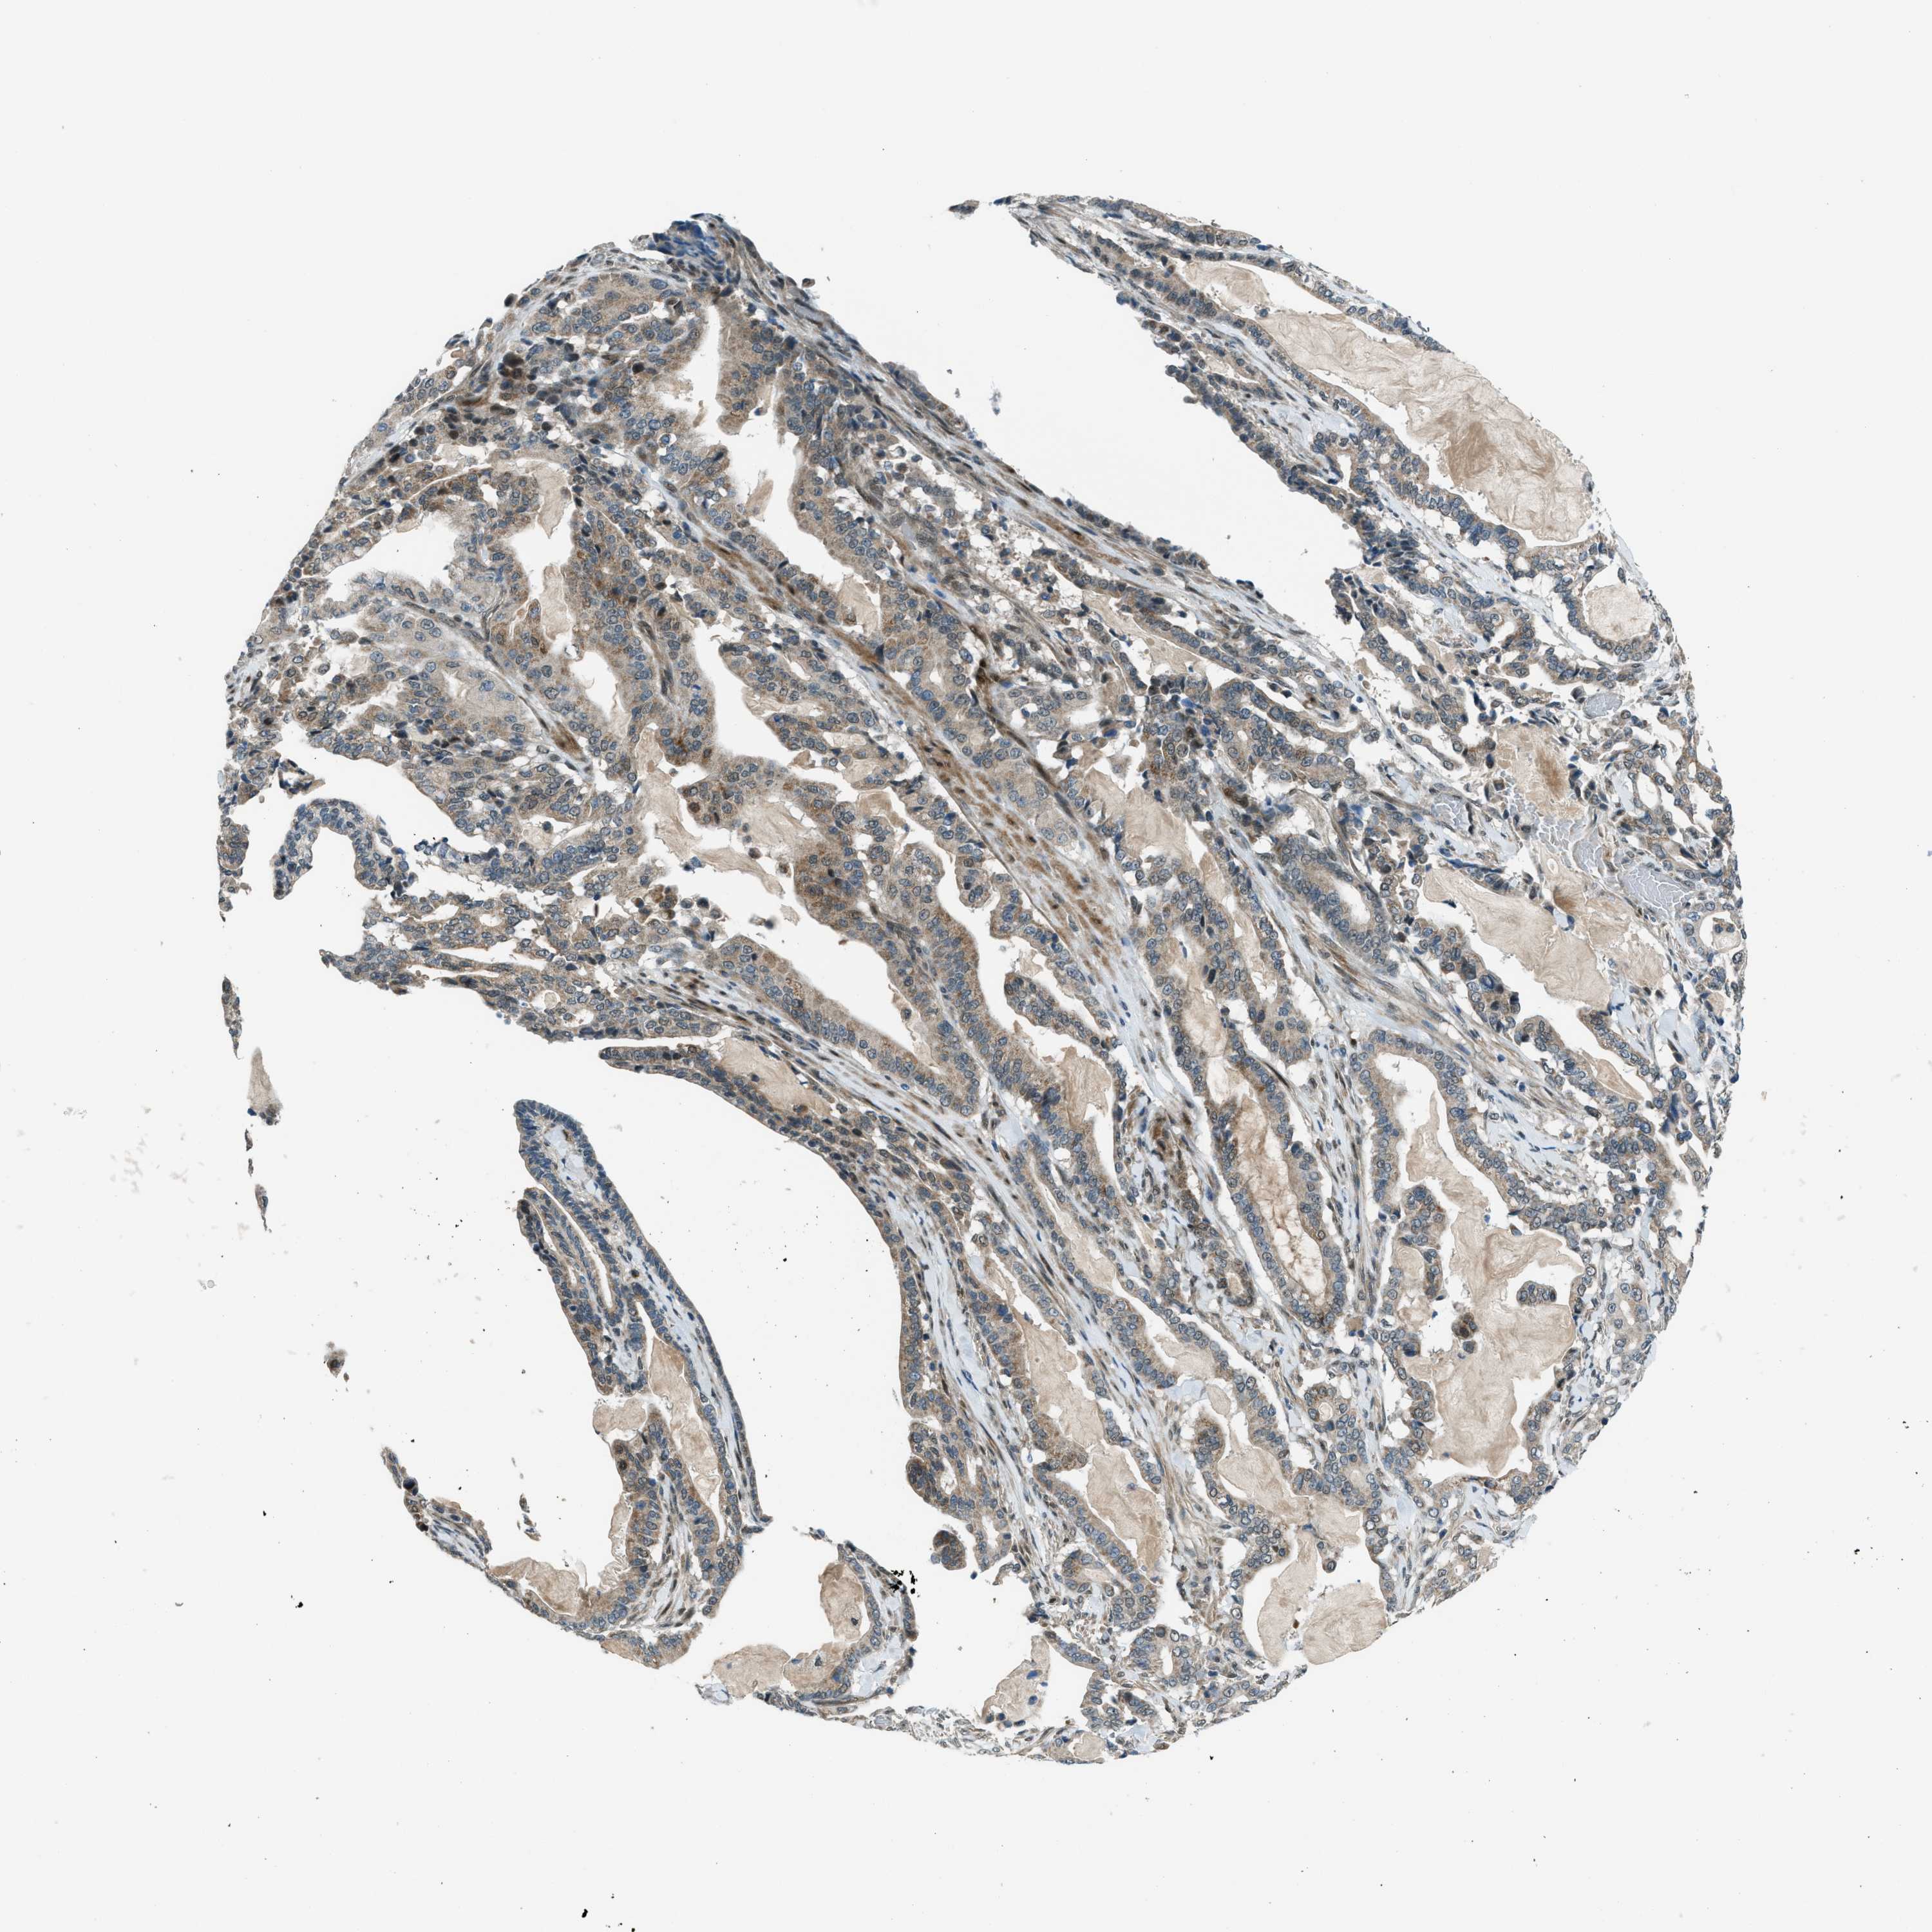

PANCREATIC CANCER - Protein expressioni

A mouse-over function shows sample information and annotation data. Click on an image to view it in a full screen mode. Samples can be filtered based on level of antibody staining by selecting one or several of the following categories: high, medium, low and not detected. The assay and annotation is described here.

Note that samples used for immunohistochemistry by the Human Protein Atlas do not correspond to samples in the TCGA dataset.

Antibody stainingi

Antibody staining in the annotated cell types in the current human tissue is reported as not detected, low, medium, or high, based on conventional immunohistochemistry profiling in selected tissues. This score is based on the combination of the staining intensity and fraction of stained cells.

Each image is clickable and will lead to virtual microscopy that enables deeper exploration of all samples and also displays staining intensity scores, fraction scores and subcellular localization as well as patient and tissue information for each sample.

Antibody HPA036356

Antibody CAB004986

Antibody CAB017025

Staining

High

Medium

Low

Not detected

Intensity

Strong

Moderate

Weak

Negative

Quantity

>75%

75%-25%

<25%

None

Location

Nuclear

Cytoplasmic/membranous

Cytoplasmic/membranous,nuclear

Adenocarcinoma, NOS

Adenocarcinoma, metastatic, NOS